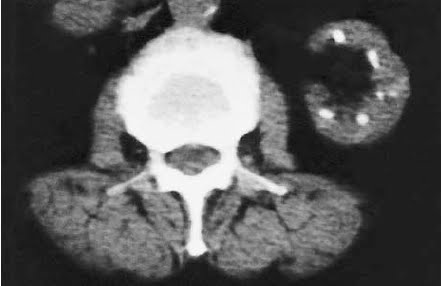

Phenacetin, whose main metabolite is acetaminophen, was originally believed to be the cause. But this was challenged by the appearance of cases where phenacetin was not involved. The modern definition of analgesic nephropathy does not mention phenacetin: “a slowly progressive disease resulting from the daily use for many years of mixtures containing at least two anti-pyretic analgesics and usually caffeine or codeine (or both), which may lead to psychological dependence”. The diagnosis is made based on pathgnomic appearances on non-contrast CT (reduced renal size, bumpy contours and papillary calcifications) in the appropriate clinical context.